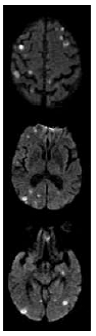

- TC craneal (8/11/2011): Sin contraste porque el paciente no tolera la prueba. Se observa edema vasogénico que

no afecta a córtex, es bilateral y tampoco sigue una clara disposición vascular. Múltiples nódulos.

- Broncoscopia: nocardiosis

Nota: Siempre que veamos una ausencia de respuesta a tratamiento betalactámico convencional pensaremos en esta